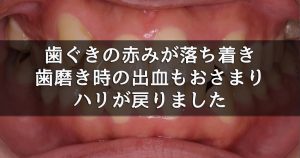

3週間後の再評価では、歯肉の発赤が明らかに改善し、腫れも引いてポケット深さは2~3 mmに改善。歯磨き時にも出血しなくなりました。

3週間後の再評価では、歯肉の発赤が明らかに改善し、腫れも引いてポケット深さは2~3 mmに改善。歯磨き時にも出血しなくなりました。